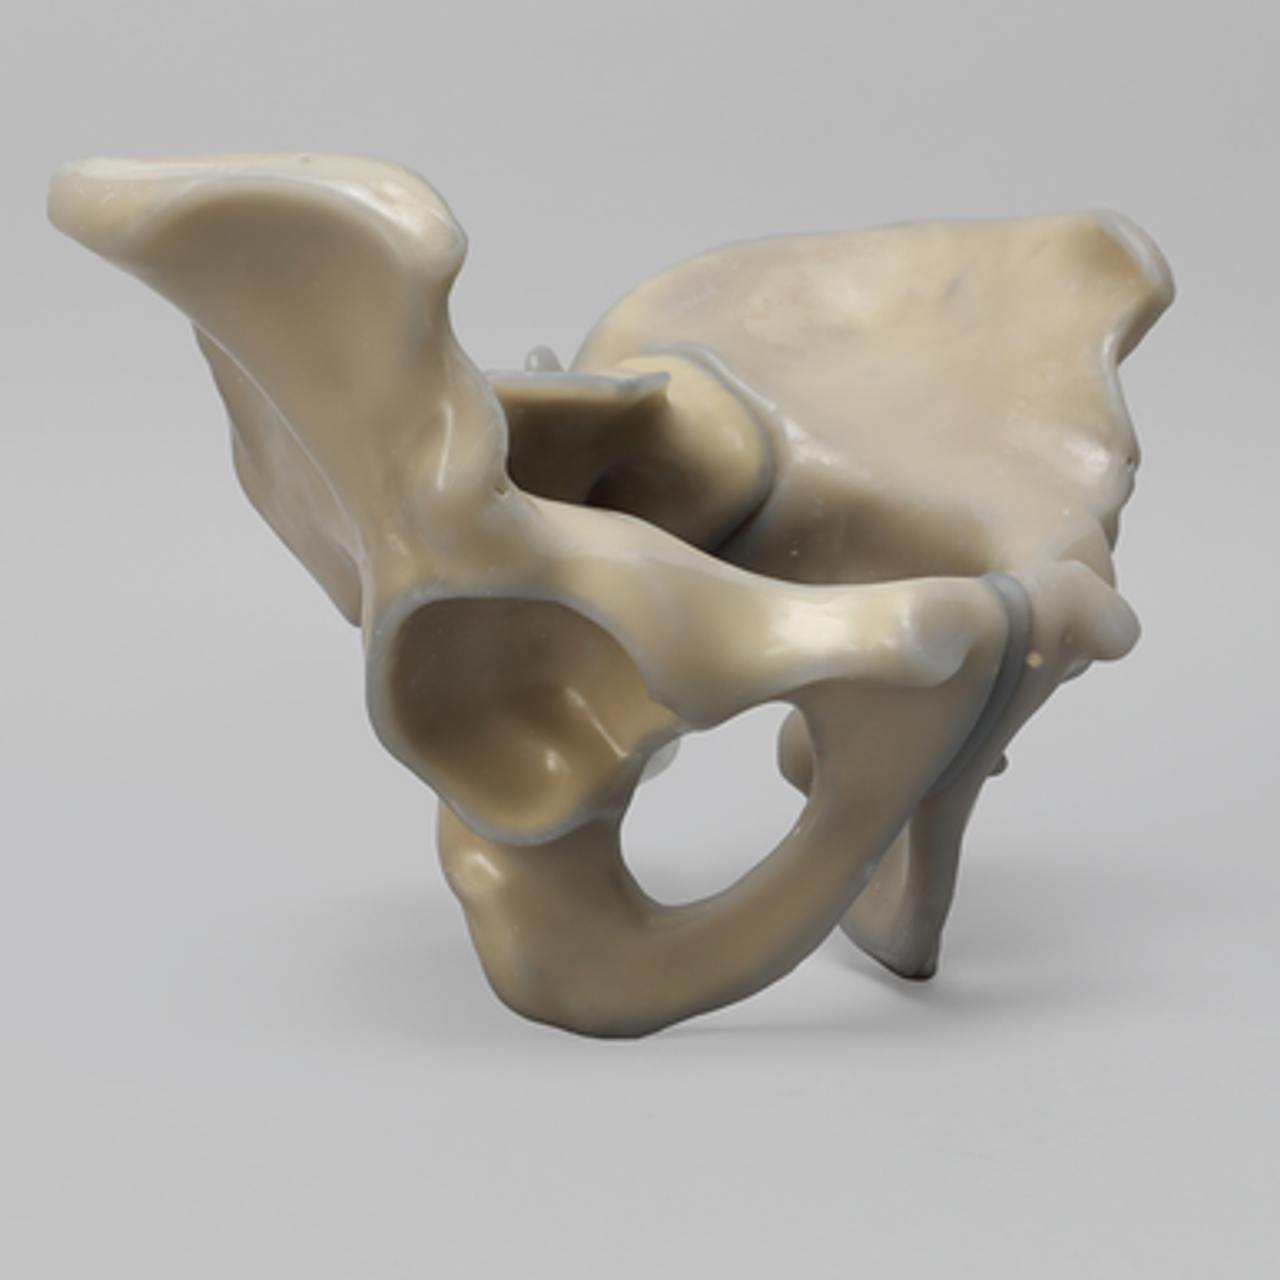

人工骨骨盆模型3415

人工骨模型,完整男性骨盆,absolute™ 第四代,17 PCF 实心泡沫芯,大号

用于力学测试的完整男性骨盆

我们的 absolute™ 骨模型 精确模拟人体骨骼的结构与力学特性,能够帮助科研人员和医疗器械企业在开发与审批过程中,轻松且经济地再现载荷与运动场景。该模型特别适用于生物力学研究、医疗器械测试及教学演示。

| 解剖部位 (Anatomy) | 骨盆 – 完整 |

| 模型类型 (Model Type) | absolute™ 骨模型 |

| 材料 (Material) | absolute™ |

| 尺寸 (Size) | 大号 |